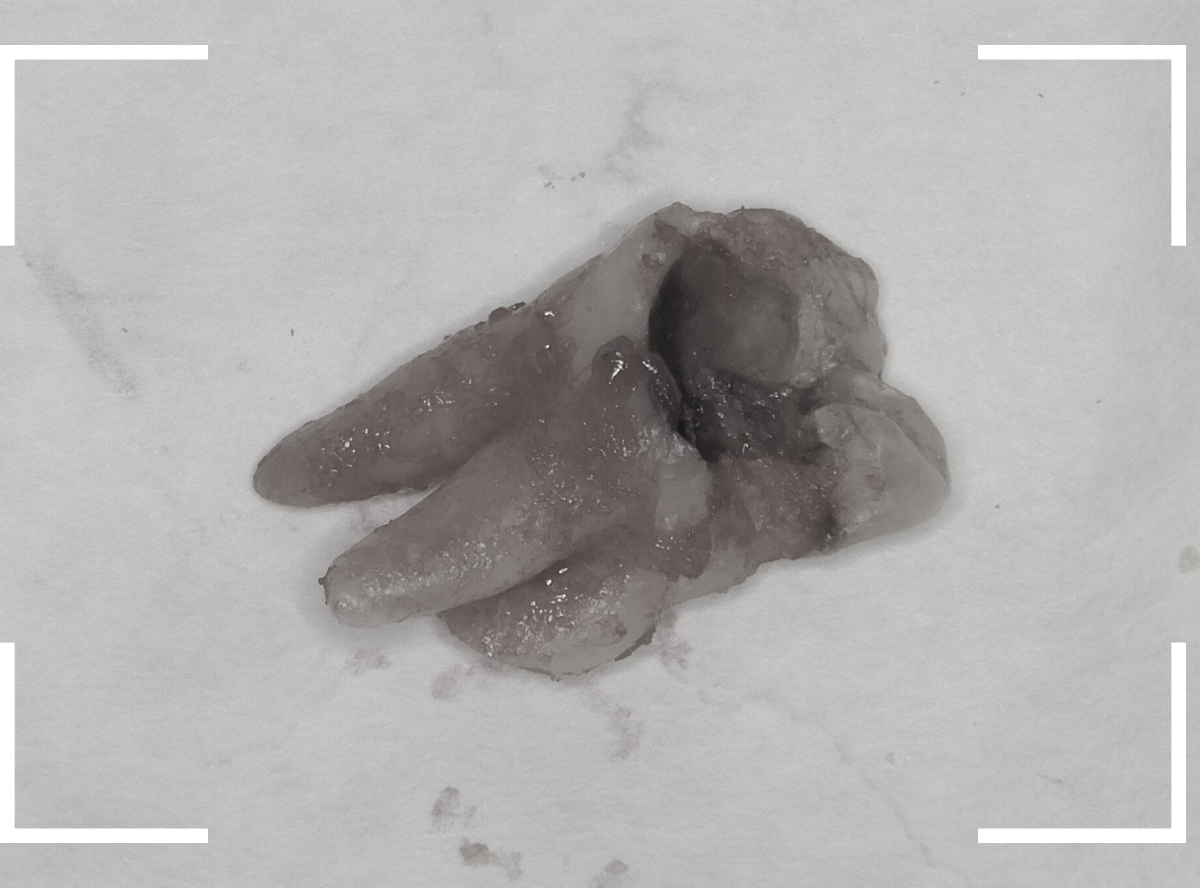

こちらが、抜歯後の写真です。

ここまで虫歯が進行していると、虫歯の治療をしても、ほとんど歯は残っていなかったでしょう。

歯の頭が無くなってしまうと、抜歯も困難にな行ってしまいます。

少しでも虫歯が進行しないうちに、と抜歯を行いましたが、やはりかなり手こずりました。

抜歯した手前の歯をお見せして、

「半年くらい前に受診していたら、歯を残せたかもしれない」というお話をすると、残念がっていました。